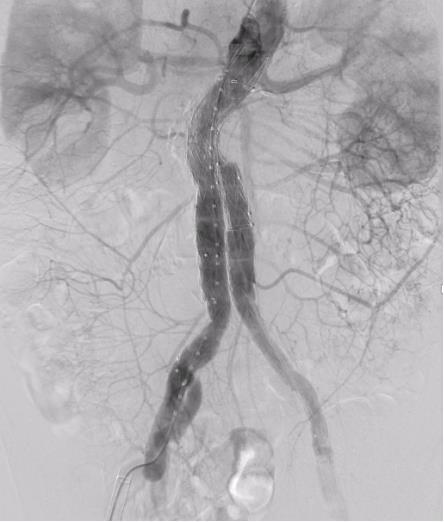

• Expert consensus on fibrin sealant aneurysm sac filling during endovascular abdominal aortic aneurysmal repair

Abstract:Abdominal aortic aneurysm is a potentially fatal vascular disease commonly encountered in the elderly population. Although endovascular aneurysm repair (EVAR) has become the preferred treatment modality, the incidence of postoperative endoleaks remains high (20%-40%), with more than 30% of cases requiring secondary interventions, thereby significantly compromising long-term outcomes. To standardize the application of fibrin sealant aneurysm sac filling during EVAR, the Vascular Surgery Professional Committee of the Chinese Association of Rehabilitation Medicine convened a multidisciplinary expert panel. In accordance with the RIGHT reporting guideline and the GRADE evidence grading system, and through two rounds of Delphi surveys to prioritize clinical questions combined with systematic evidence review, the committee developed the Expert consensus on fibrin sealant aneurysm sac filling during endovascular abdominal aortic aneurysmal repair. This consensus systematically addresses key aspects including indications and contraindications, technical procedures, dosage estimation, intraoperative assessment criteria, prevention and management of complications, and postoperative follow-up. It defines criteria for complete sac filling and provides tailored application strategies under various anatomical conditions. The aim of this consensus is to standardize clinical practice, reduce the incidence of endoleaks, improve long-term outcomes after EVAR, and provide vascular surgeons with evidence-informed and practically applicable guidance.